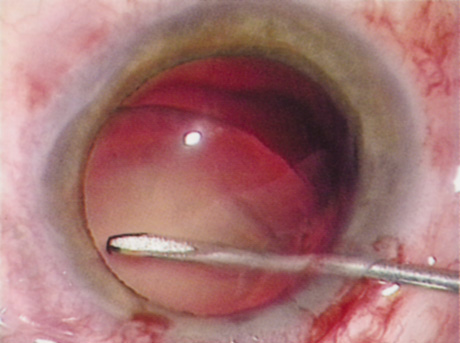

Retrobulbar blocks were among the earliest of orbital block techniques and have stood the test of time. Although there are many approaches to block administration, each technique intends delivery of the anesthetic medication into the intraconal space. These blocks are highly effective (about 95%) in achieving adequate ocular akinesia and anesthesia. Potential complications include retrobulbar hemorrhage,67 globe penetration,68,69 optic nerve sheath hemorrhage, extraocular muscle toxicity with persistent diplopia, and, rarely, brainstem anesthesia. Visualization of the globe is improved when using a transconjunctival approach (Fig. 6) or when the skin is indented with a cotton-tipped applicator (Fig. 7), making globe perforation less likely.

Fig. 6. Retrobulbar block using a transconjunctival approach.

Fig. 7. The skin is indented with a sterile cotton-tipped applicator until it is past the equator of the globe, thereby reducing the risk of globe perforation when the needle is inserted.